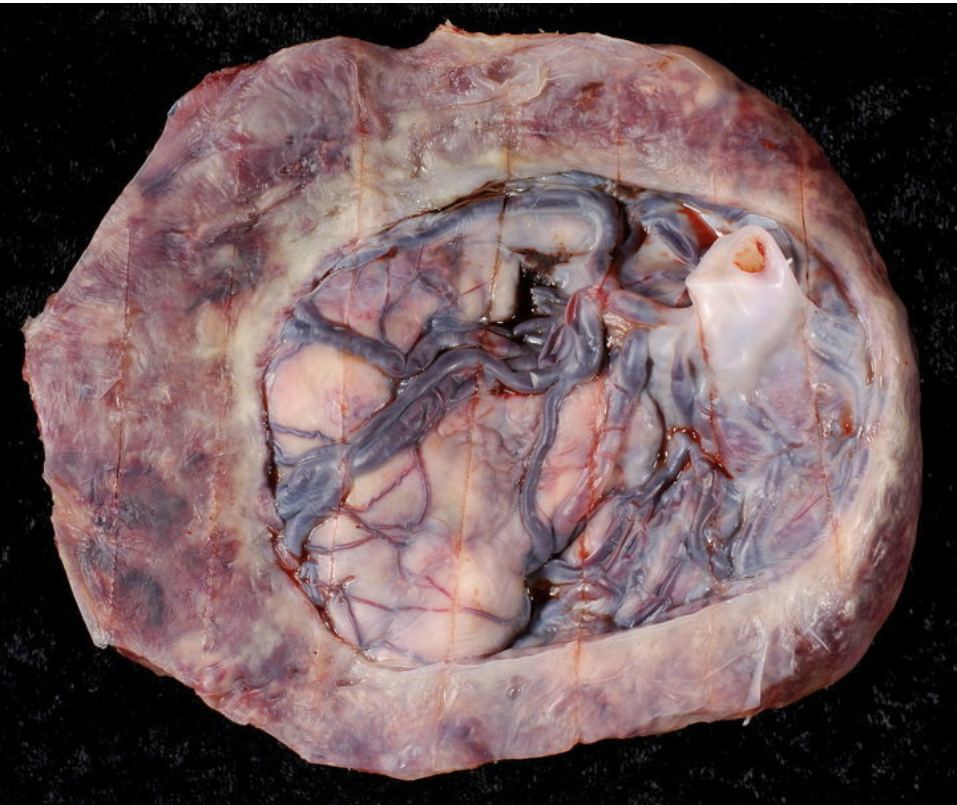

In circumvallate placenta, the chorionic plate is _____ than the basal plate.

Hint: larger/smaller